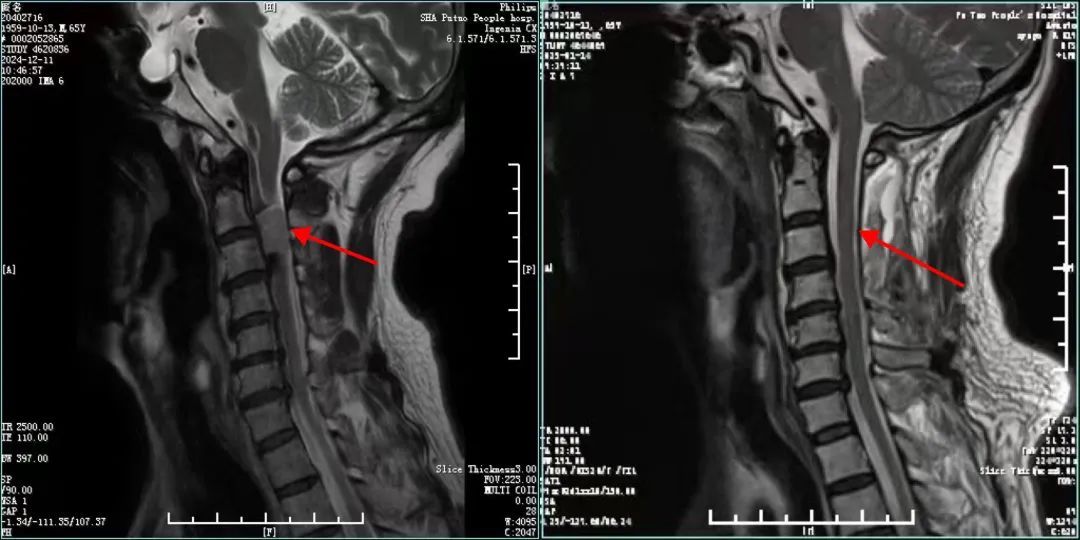

手术前(左)后(右)对比

一个多月前,65岁的周先生因颈椎不适,来到人民医院骨科就诊。“之前是脖子痛,活动受限,且偶尔双手出现放射性的疼痛和麻木,一直采用吃药、理疗等保守治疗。就诊前夕,疼痛症状突然加重,手部麻木加剧且无力。”接诊医生立即安排其做了颈椎磁共振检查。“检查显示,患者的颈2-3椎体水平椎管内(髓外硬膜下)占位,肿瘤占据椎管容积超三分之二,颈髓受压严重。”周先生被立即收治入院。

术后,患者周先生复查颈椎增强MRI、CT显示:肿瘤完全切除,脊髓压迫完全解除,内固定螺钉位置良好。他的术后病理报告显示:脊膜瘤,预后良好。医院骨科医护团队联合康复团队对周先生进行了围手术期的同步康复治疗,周先生很快恢复良好,带着颈托下床正常活动。